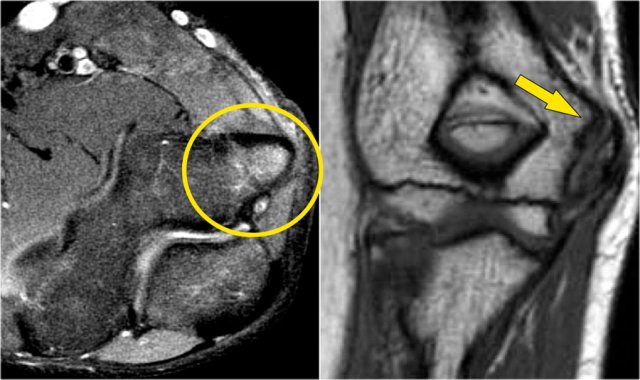

These images are of a young baseball player, who presented with elbow pain at age 14.

The T2W-fatsat image shows marrow edema and maybe there is a subchondral fracture.

Obviously someone told him to keep throwing, because he came back three years later at age 17 and you can see what can happen when they push too hard in getting these kids to become a professional.

The T1W-image shows fragmentation (yellow arrow) with a loose body (red arrow).

The T2W-image demonstrates that the fragment is unstable because there is high signal between the fragment and the humerus.

At arthroscopy there is depression and irregularity of the cartilage of the capitellum.

First the loose bodies were taken out.

Then frequently an OATS-procedure is performed, which we will discuss now.